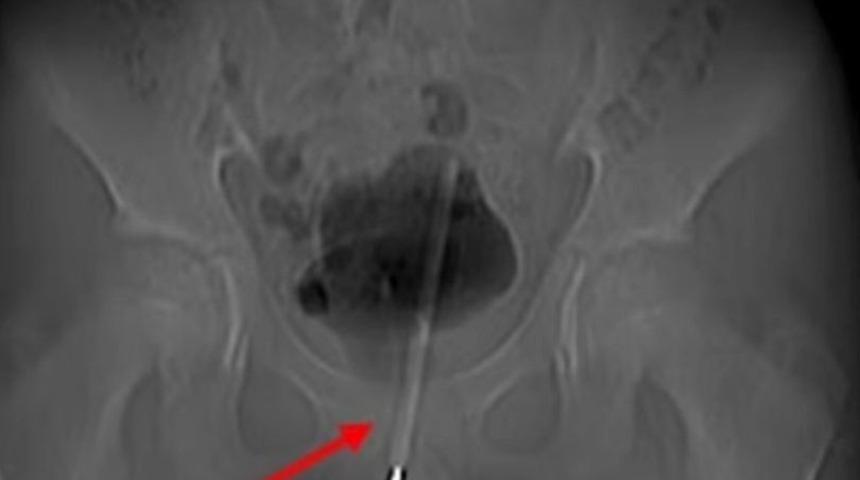

Röntgenler, termometrenin idrar yoluna o kadar sokulduğunu ve çocuğun mesanesine girdiğini ortaya çıkardıktan sonra, doktorlar anahtar deliği ameliyatı kullanarak termometreyi çıkarmaya karar verdiler. Asian Journal of Surgery'de vakayı detaylandıran ürologlar, mesaneye giden dokuda küçük bir cerrahi delik açtıklarını ve ardından termometreyi doğru konuma getirerek onu çıkarmak için küçük aletler kullandıklarını söylediler. Ameliyatın başarısına rağmen, çocuğun deneylerinden dolayı uzun vadeli herhangi bir komplikasyon yaşayıp yaşamadığına dair bir açıklama yapılmadı.